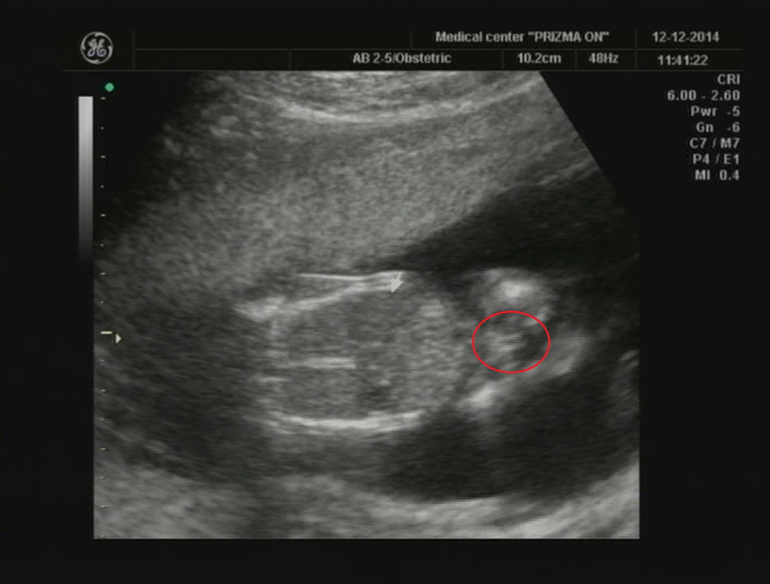

Особенности УЗИ при определении пола ребенка

Раздел: Идеи и советы